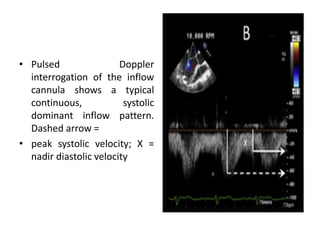

• Pulsed Doppler

interrogation of the inflow

cannula shows a typical

continuous, systolic

dominant inflow pattern.

Dashed arrow =

• peak systolic velocity; X =

nadir diastolic velocity